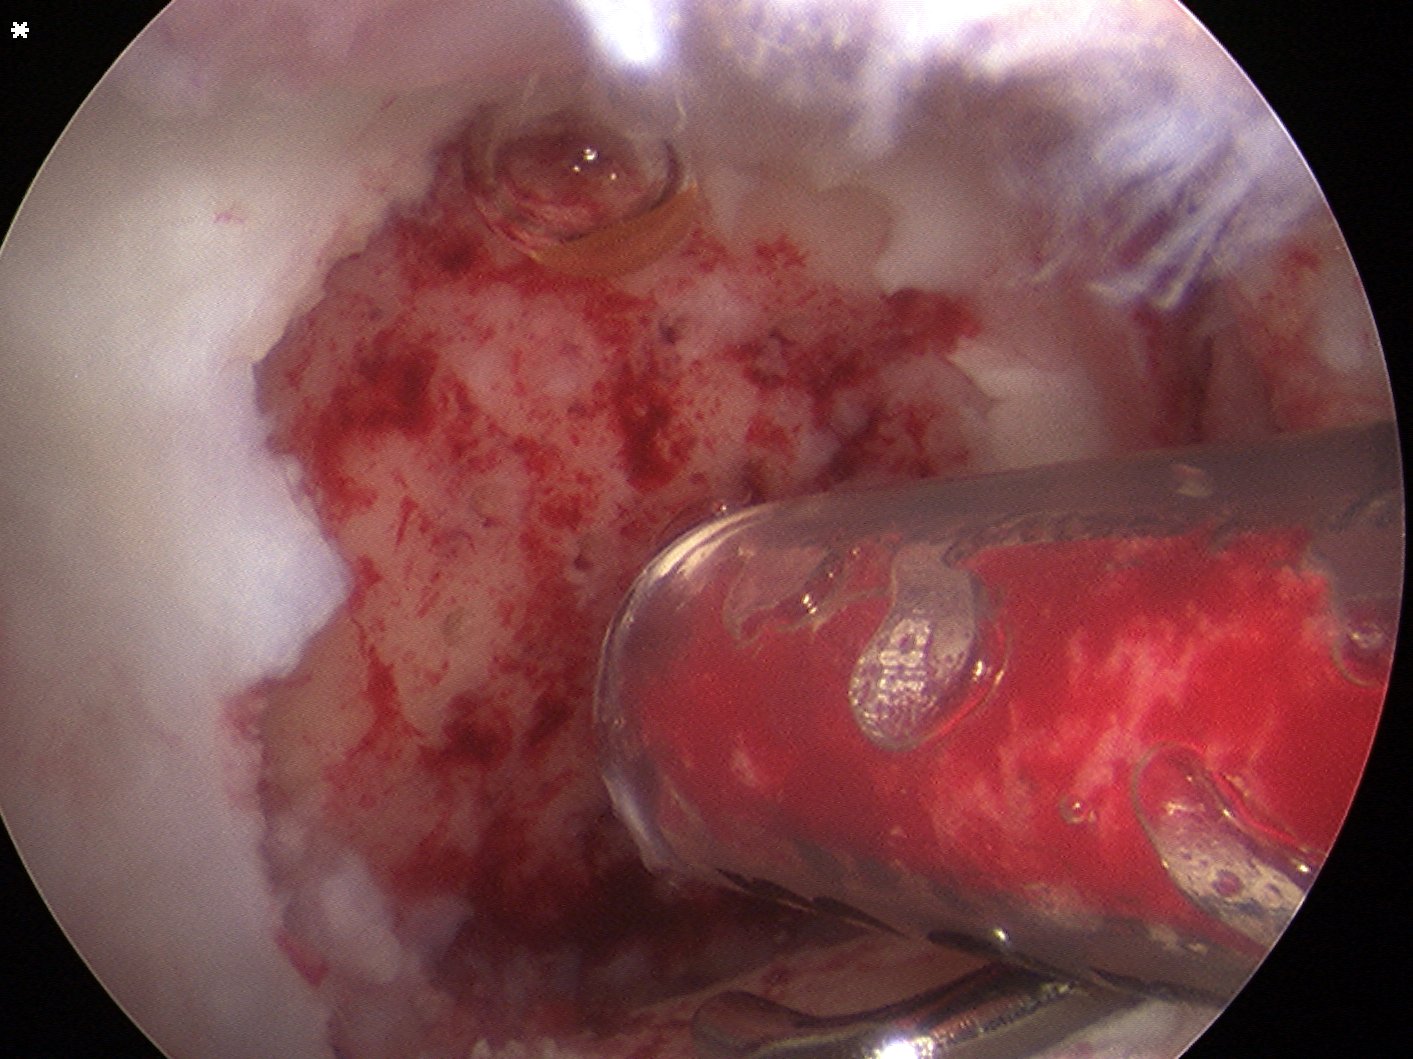

Debride base of lesion

Fibrous tissue removed meticulously from femur with curette and shaver

Take bone graft from medial tibia

- depends on amount of bony defect

- turn into paste / add blood

- put in small syringe that will fit through AM portal

- cut tip off

Use K wire to microfracture

- insert bone graft